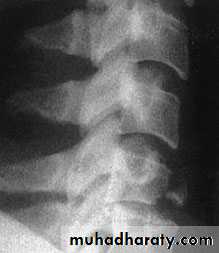

Lumbar Spine X Ray

Lateral radiograph

A/P radiograph• Sacrum